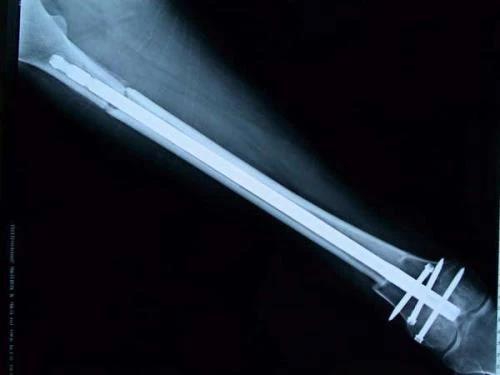

保肢治療指經(jīng)典型骨肉瘤在多學(xué)科團(tuán)隊(duì)醫(yī)生共同努力下完成的新輔助化療、保肢手術(shù)和輔助化療等一系列治療總稱,其目的是在提高患者生存率的前提下,減少局部復(fù)發(fā)、盡量保留良好的肢體功能。肢體經(jīng)典型骨肉瘤保肢治療方法如下圖所示:

新輔助化療的目的是盡早殺滅遠(yuǎn)處微小轉(zhuǎn)移灶,縮小腫瘤及周圍炎性水腫反應(yīng)區(qū),以利于后續(xù)的保肢手術(shù);觀察腫瘤對化療的敏感性,為進(jìn)一步指定個(gè)體化的術(shù)后化療方案奠定基礎(chǔ)。骨肉瘤新輔助化療下的保肢治療如下圖所示: